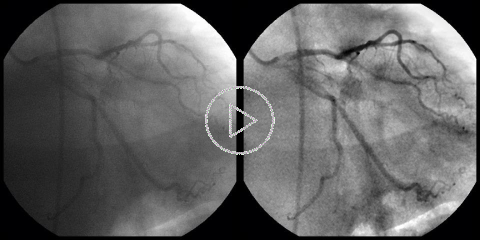

Cardiac DSA:

This is our first attempt to bring Digital Subtraction Angiography (DSA) to cardiology, where the motion of the heart precludes the use of the classic, static DSA. The Coronary DSA solution, presented here, is built around our GPU accelerated algorithms for the elastic image registration. Suppression of the "background" anatomy improves contrast and visibility of the blood vessels, which can be especially important in the case of a heavier patient. Our Cardiac DSA viewer does not require selection of any mask image(s) or pre-detection of blood vessels. Instead, it builds the subtraction mask dynamically, separating the image of the blood vessels from the rest of the anatomy in consecutive frames.